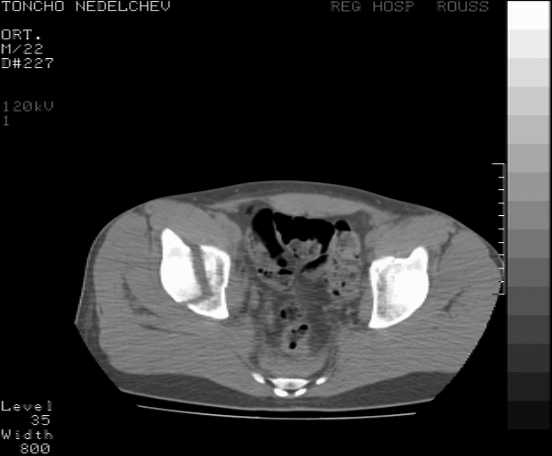

Here are some more axial images. What is your opinion as for the timing of the operative treatment?

Yordan! In this case position of bone fragments is quite good. We

prefer to use miniinvasive technique. We fix posterior column by can. screw and put 3mm pin with distal thread to the anterior column. Next day after the surgery he may start walking with crutches. 3 month after the surgery we remove the pin. In cases of maleolar fractures we use